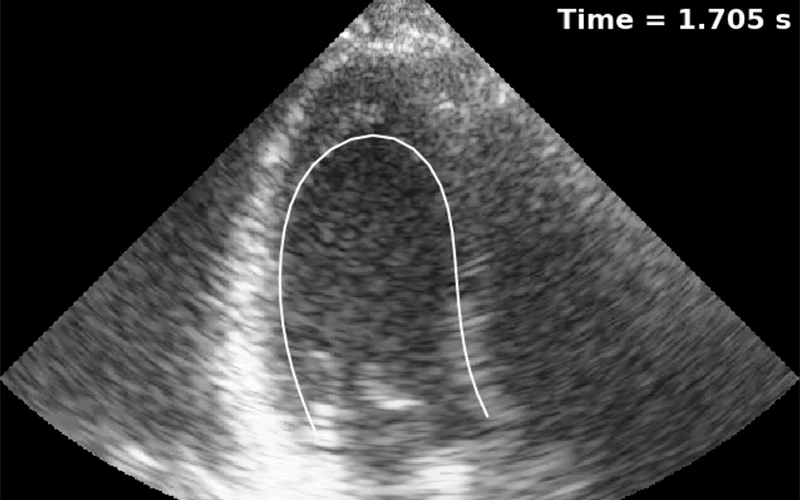

Veocor has developed the first cloud-based tool to diagnose the risk of cardiac thrombus formation and associated stroke. Veocor’s AI-powered technology quickly analyzes standard ultrasound images to provide a measure of blood flow in the left ventricle and identify regions at risk of thrombus formation. No additional hardware or training is required: cardiologists will be able to risk-stratify patients and identify who would benefit from anticoagulation.